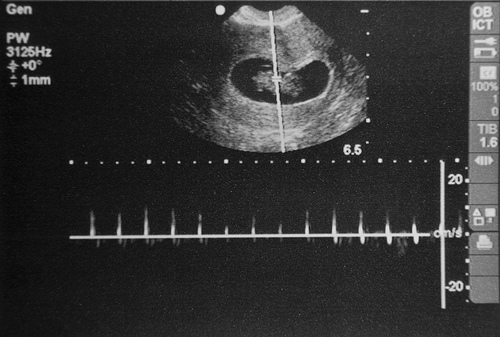

ultrassom de 5 semanas

Ultrassom de 5 semanas de gravidez com batimentos cardíacos.